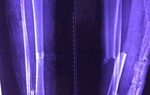

Trước đó, như PNVN đã đưa tin, vào ngày 29/9, Bệnh viện Quận 11 đã mổ thành công cho bệnh nhân Lê Thị Ngọc D. (Sn 1978, ngụ tỉnh Long An) bị gãy chân bên phải (đoạn ống quyển) thành 2 đoạn phức tạp kèm theo tứ chứng Fallot (bệnh tim bẩm sinh) nguy hiểm, rất dễ tử vong trên bàn mổ. Trước đó, bệnh nhân này đã bị một số bệnh viện từ chối mổ.

Trong ca mổ này, các bác sĩ quyết định không gây mê toàn thân vì nguy hiểm mà chỉ thực hiện phẫu thuật kết hợp xương bằng phương pháp gây tê mỗi vùng cẳng chân dưới sự hướng dẫn của sóng siêu âm, nhằm giúp đưa thuốc tê chính xác vào dây thần kinh cần gây tê. Điều này sẽ không ảnh hưởng đến vấn đề huyết động, có nghĩa ca mổ ghép xương sẽ ít ảnh hưởng do tứ chứng Fallot gây ra trên bàn mổ.